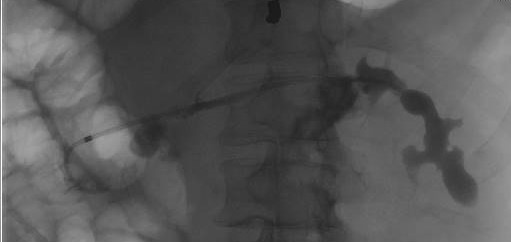

#TakeoverTuesday With world-renowned faculty

@IUGastro @ Advance Endoscopy (AE) Training is one of the best in the country.

Dr. Stuart Sherman @studabaka and @MunishAshatMD

(AE Fellow) successfully treating a pancreatic duct disconnection with PD stenting.

English